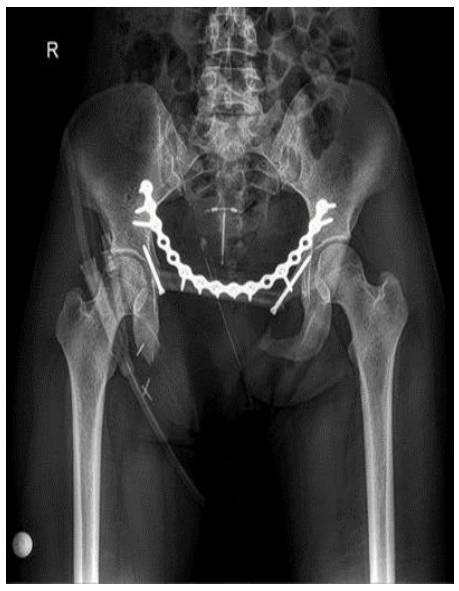

Taramalarında metastaz saptanmayan hastaya neoadjuvan 4 kür kemoterapi verildikten sonra Tip 3 rezeksiyon ve fibula/titanyum plak ile rekonstrüksiyon uygulandı

Ameliyat Sonrası: Rezeksiyon sonrası fibula ve plak/vida ile yapılan rekonstrüksiyon görülmekte